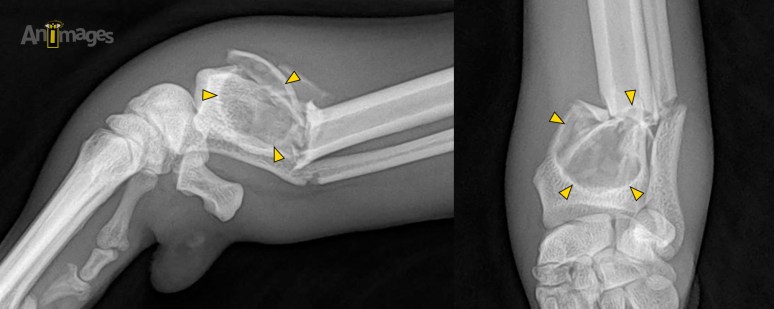

D’abord, ces clichés montrent un épaississement sévère des tissus mous de l’antébrachium gauche, surtout distalement. Au même niveau, une fracture complexe traverse la diaphyse de l’ulna et la métaphyse radiale, avec un déplacement modéré des segments. La fracture radiale survient à l’aspect proximal d’une large (17 mm) lésion ostéolytique de configuration géographique qui est entourée d’une paroi minérale relativement nette. Cette lésion a provoqué une expansion de la cavité médullaire jusque dans l’épiphyse, sans toutefois atteindre l’articulation. Les cortex sont amincis et incurvés crânialement et médialement, signifiant la croissance lente d’une lésion intramédullaire suffisamment chronique et faiblement active pour susciter ce remodelage cortical. L’amincissement cortical et la lyse des trabécules osseuses a engendré plusieurs points de faiblesse qui ont cédé lorsque le chien jouait.

Ces caractéristiques sont celles d’un kyste osseux, qui a été confirmé histologiquement chez ce chien de 6 ans. Cette pathologie osseuse rare affecte certains chiens comme les humains, sans race de prédilection. Les chiens affectés sont généralement plus jeunes (moins de 18 mois en moyenne)(1,2) que ceux affectés par un sarcome osseux (ostéosarcome surtout), mais le diagnostic peut être retardé jusqu’à ce que le kyste soit suffisamment large pour créer un inconfort, ou lorsqu’une fracture survient. Lors de fracture pathologique, la boiterie est généralement aiguë et sévère. Un kyste aneurysmal – une autre forme plus rare de kyste – peut croître en réponse à une anomalie vasculaire (fistule artério-veineuse). La transformation maligne de ce type de kyste a déjà été rapportée (2).

Notez l’absence de prolifération osseuse et les marges relativement nettes de cette lésion lytique, des caractéristiques en faveur d’un kyste plutôt que d’un sarcome osseux. Certaines tumeurs médullaires – notamment le myélome multiple, le plastocytome et certains lymphomes – peuvent toutefois présenter des caractéristiques radiographiques similaires, justifiant une cytoponction ou une biopsie de la lésion avant l’intervention chirurgicale, surtout si un pronostic précis doit être établi auparavant.